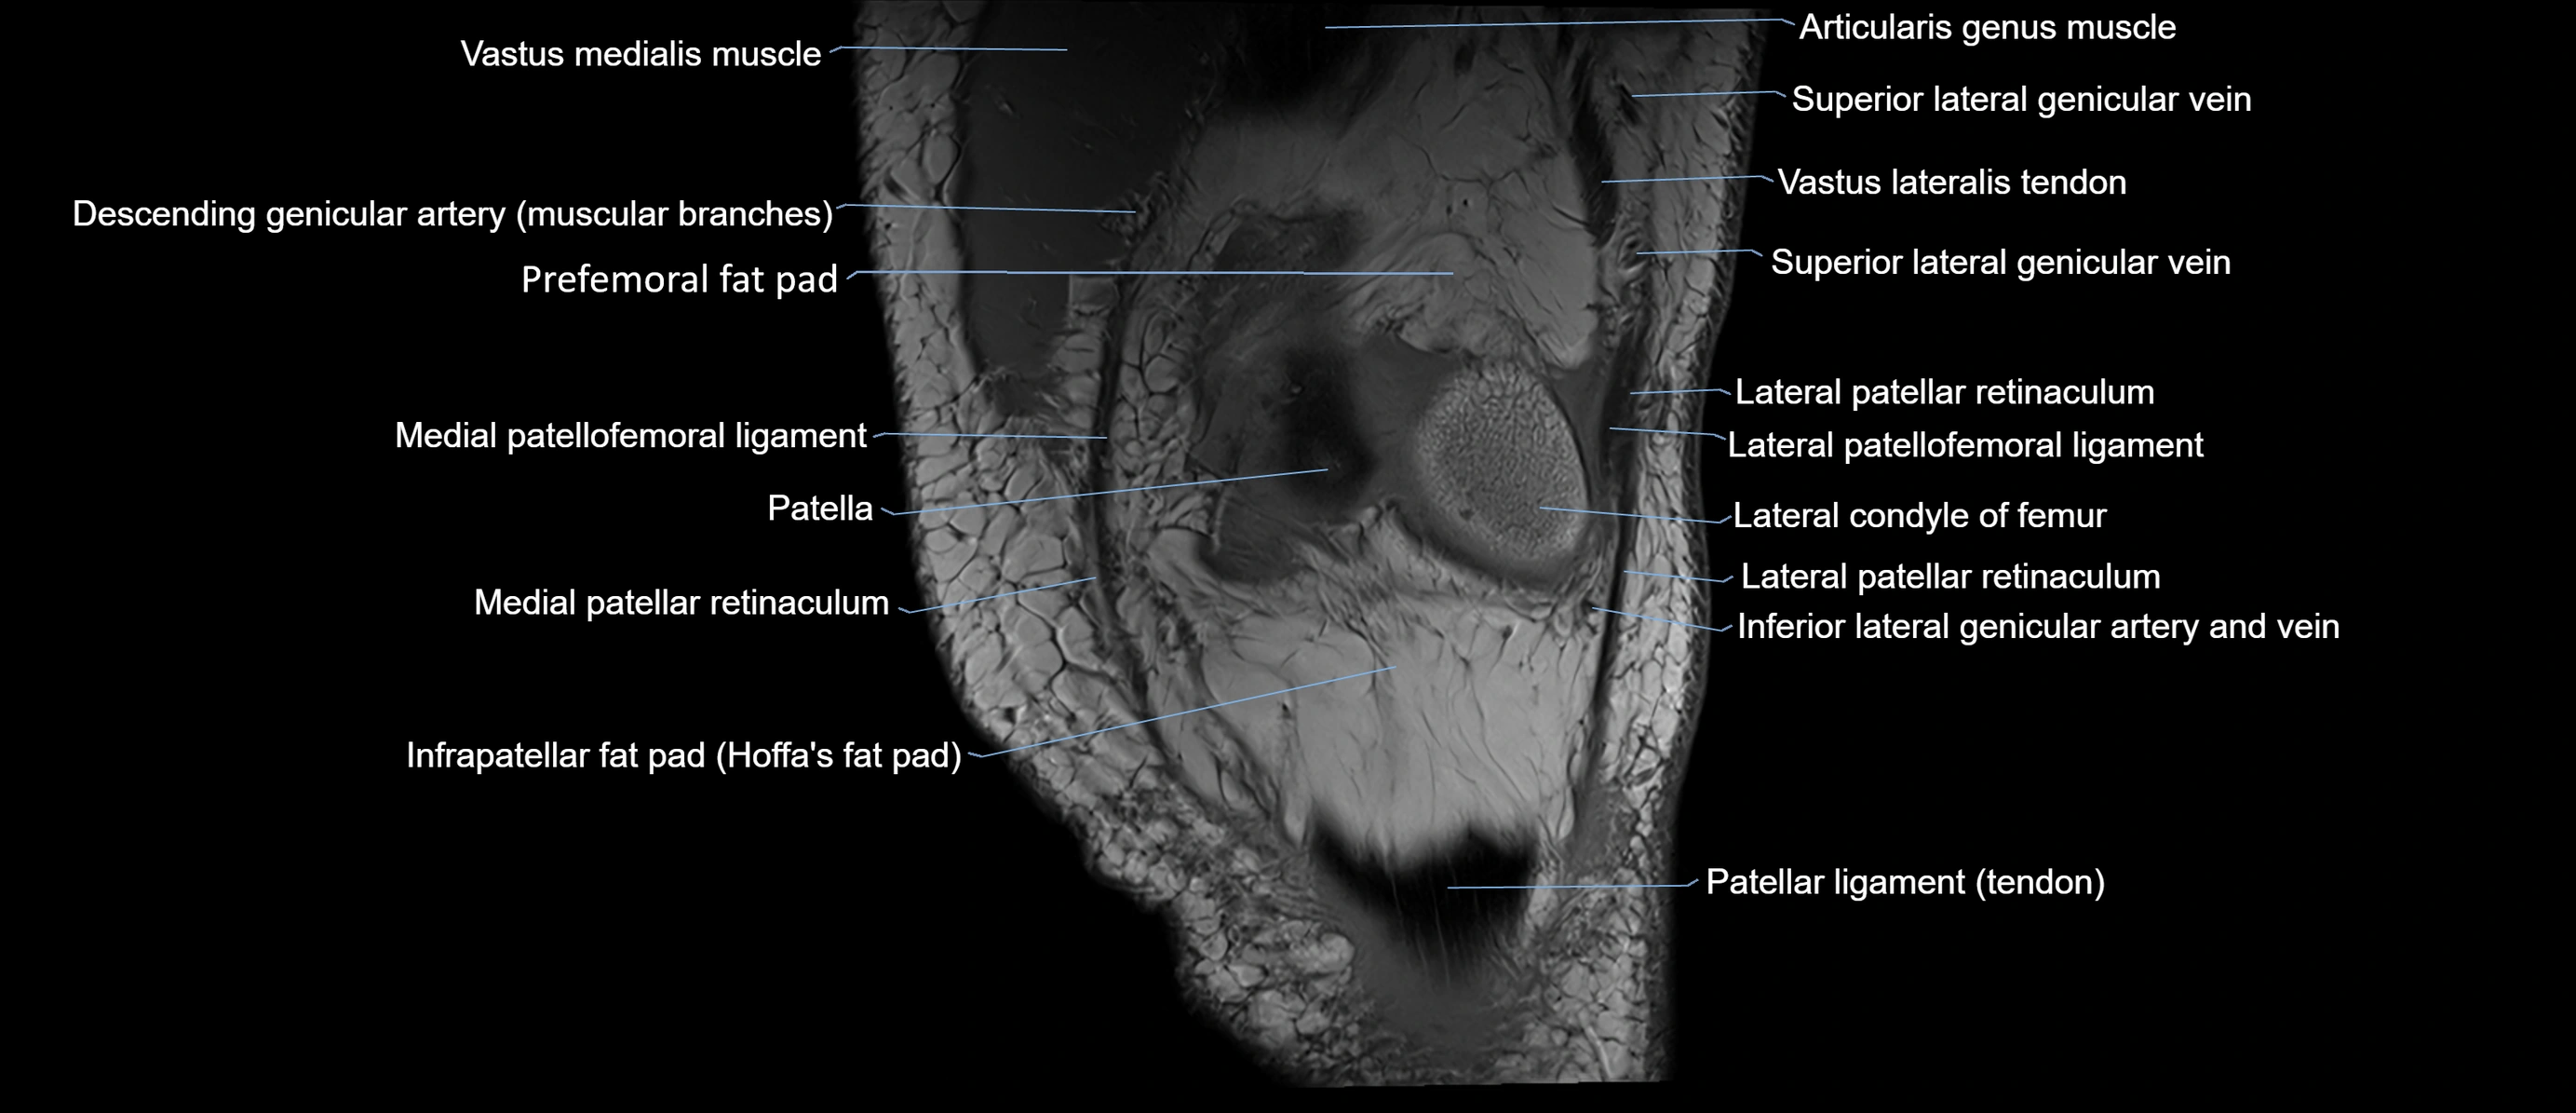

- Infrapatellar fat pad

- Lateral patellar retinaculum

- Lateral patellofemoral ligament

- Medial condyle of femur

- Medial patellar retinaculum

- Medial patellofemoral ligament

- Patella

- Patellar tendon (patellar ligament)

- Prefemoral fat pad

- Superior lateral genicular vein

- Vastus lateralis muscle

- Vastus medialis muscle